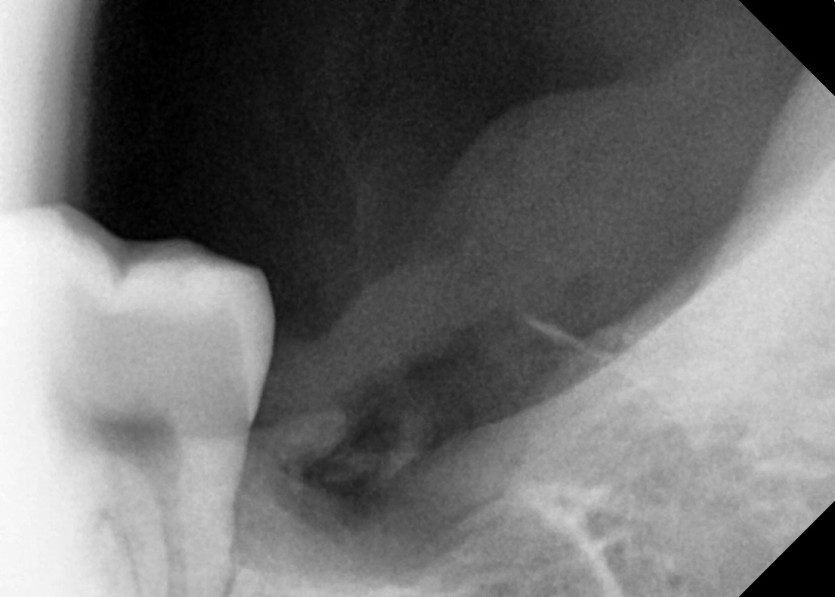

#38 사랑니 발치

구강 외과 전문의가 당일 발치했습니다.